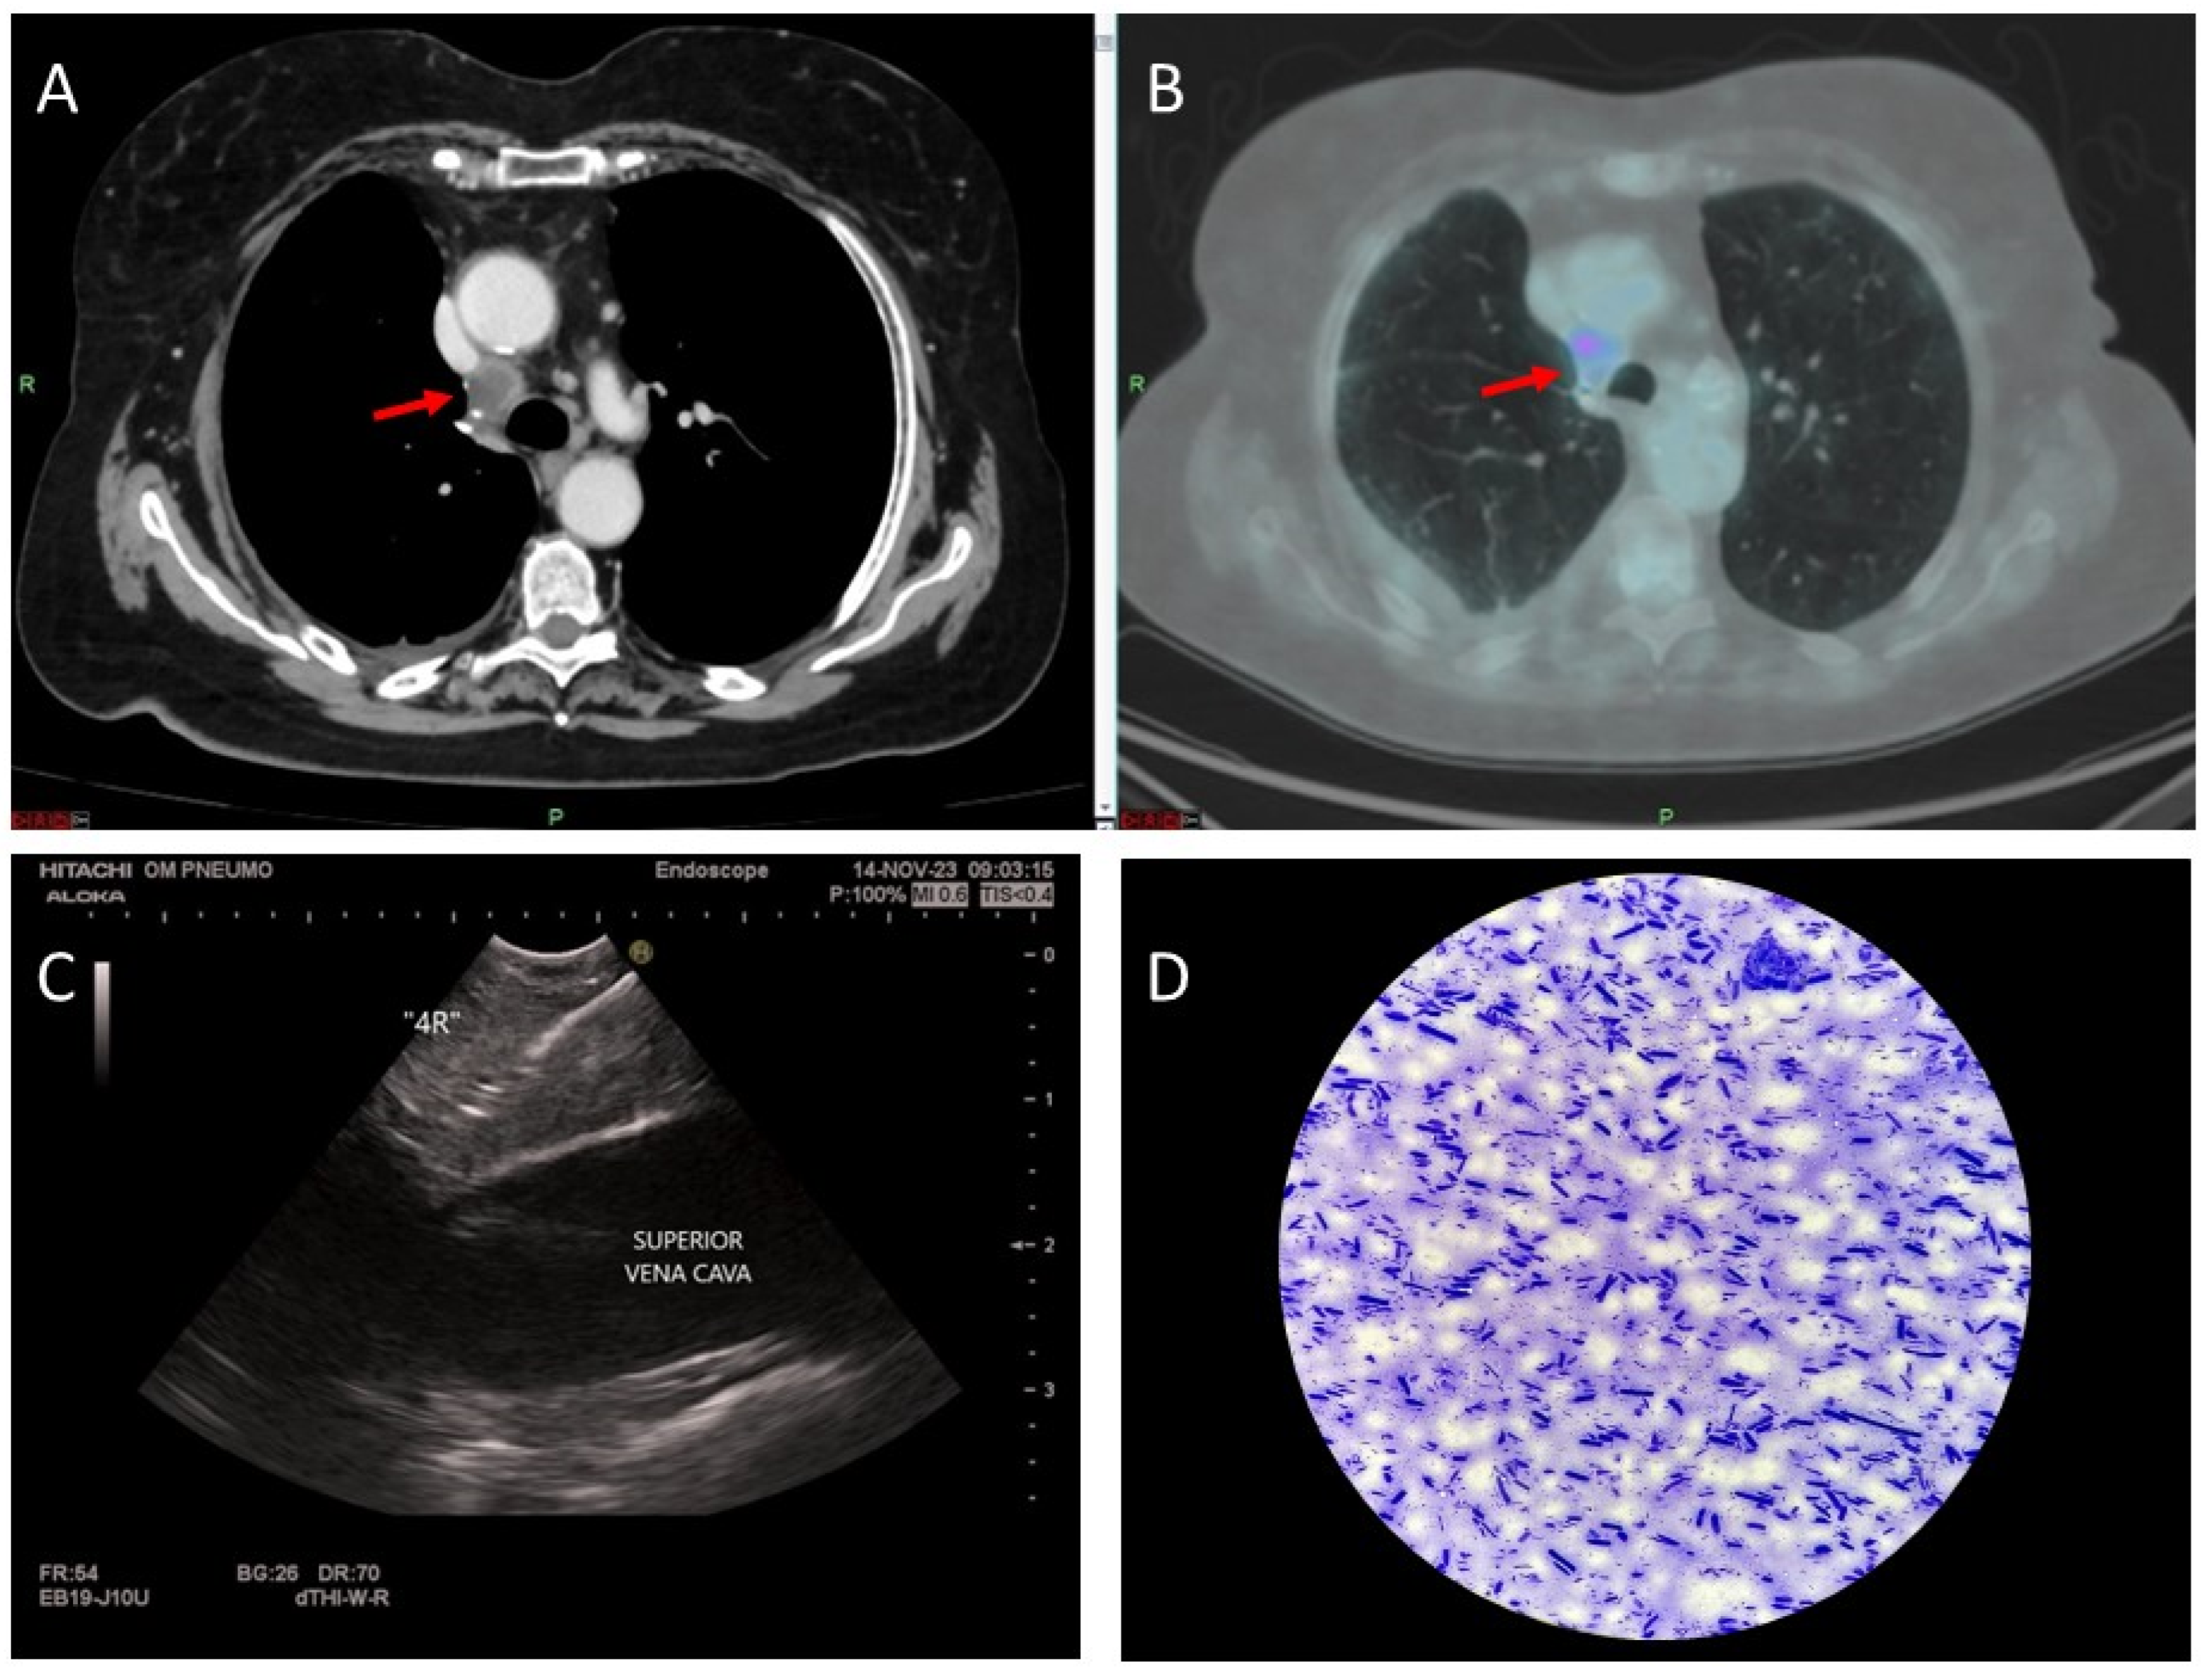

1.1. Abstract 1 (Oral Presentation): Feasibility and Safety of Transvascular Endosonography: A Case Series

Cristina Albrici, Carmine Salerni, Simone Contino, Paolo Carlucci, Stefano Centanni and Michele Mondoni

• Respiratory Unit, ASST Santi Paolo e Carlo, San Paolo Hospital, Department of Health Sciences, University of Milan, Milan, Italy

Background: Endosonography is the preferred technique for diagnosing mediastinal lymphadenopathy and the gold standard for mediastinal staging of lung cancer. The presence of major vessels interposed between the airways/oesophagus and the target lesion has long been regarded as a concern for major bleeding. Recent scientific evidence, mostly based on case reports/series, have demonstrated the feasibility and the safety of traversing major thoracic vessels to sample lymph nodes or lung lesions. However, most of the reported cases were based on EBUS-TBNA.

Methodology: We herein present a case series of six transvascular endosonographies in which three patients underwent EUS-B-FNA without any complication (Figure 1).

Demographic, clinical and procedural data were collected and summarized in Table 1.

Results: Diagnosis of malignancy was obtained by endoscopic procedures in 5 out of 6 patients with an overall diagnostic yield of 83.3%, in accordance with recent meta-analyses reporting an overall accuracy of 82.1–85%. 3.5 (0.5) mean (standard deviation) needle passes were performed. No major complications were noted. A mild endobronchial bleeding was recorded in a single case. No haematomas or pseudo-aneurysms were reported. All the patients were monitored for at least three hours after the procedure and contacted in the following days to record any complication.

Transvascular approach should be considered only when the result of the biopsy will significantly impact patients’ management and outcomes even though literature reports a low incidence of major adverse events (2.7%) with an incidence of bleeding of any severity of 1.4%. Indeed, possible complications following the puncture of intrathoracic vessels may be represented by fatal haemorrhage, intramural hematoma, pneumomediastinum and tracheal stenosis due to hematoma compression.

Conclusions: Transvascular approach during conventional EUS-FNA has been frequently reported in the literature but to our knowledge, only one case report is available on transvascular EUS-B-FNA. In this case series we confirm the good accuracy and safety of transvascular endosonography of mediastinal lymph nodes and pulmonary lesions. We first demonstrate, in a larger number of patients, that transvascular EUS-B-FNA is a useful and safe technique.

Further research, based on a larger cohort of patients, are warranted to validate our findings.